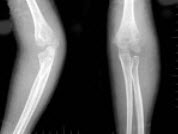

32、单项选择题

男孩,13岁,外伤后入院。结合图像,最可能的诊断是()

A.青枝骨折